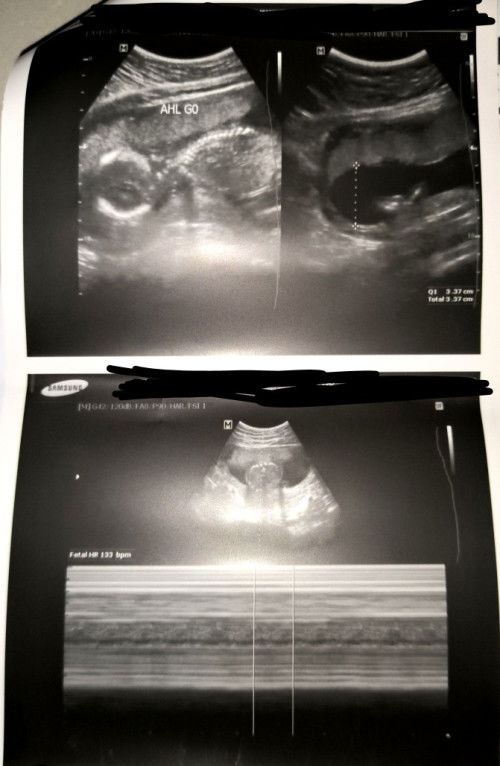

18w3d utz 🫶🏻🫶🏻🫶🏻

Low lying placenta

position ng baby

hello po mga mi. ask ko lang po kung mababago pa kaya yung position ni baby hanggang bago ako manganak? 5 months and 3 days na po kami. eto po yung result ng ultrasound saken.